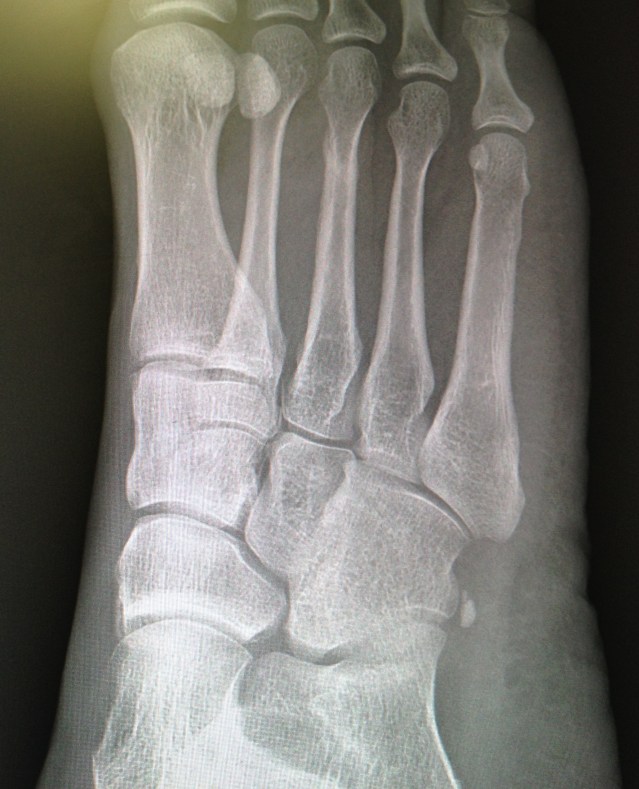

Two weeks ago, I returned to Dr. Geller, the orthopedic podiatrist who’s been treating my most-recent stress fracture. He x-rayed the site of the injury, and gave me the green light – healed! You can see it in the middle metatarsal: a faint, swirly milky way of new bone. I can finally put seven weeks of recovery behind me. Now, it’s time for next steps.